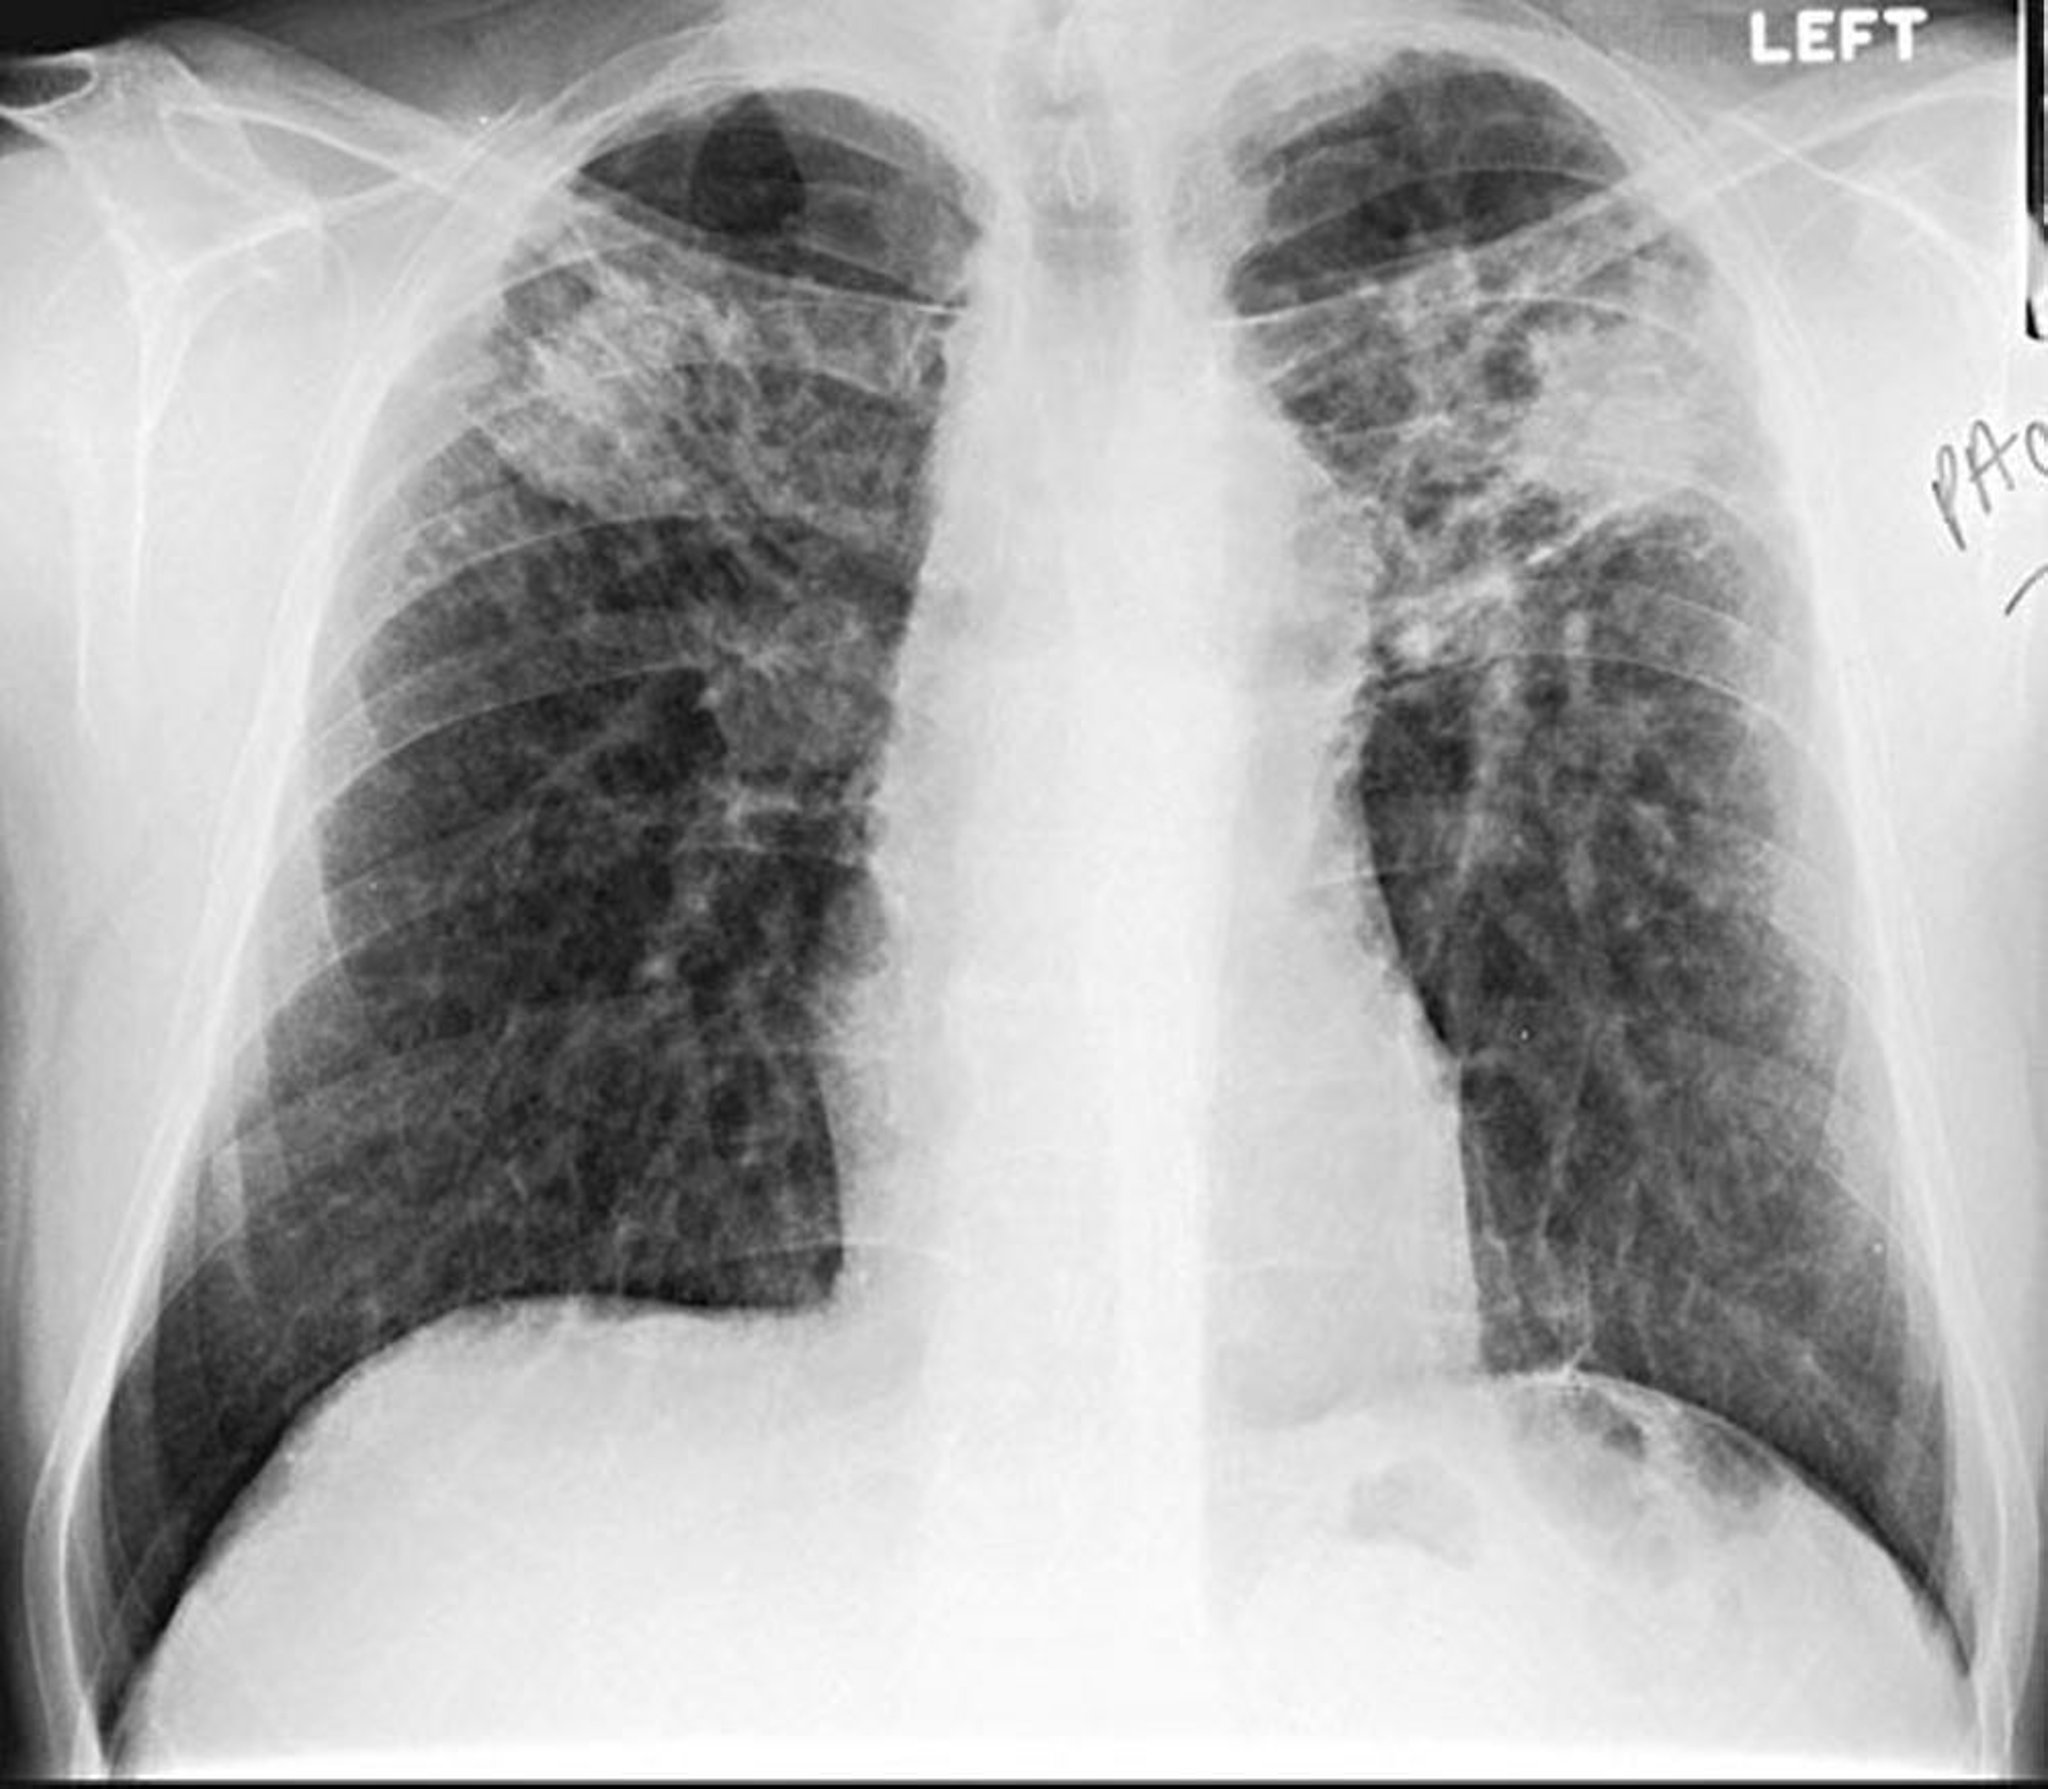

Silicosis: forma con conglomerados

Image courtesy of David W. Cugell, MD.